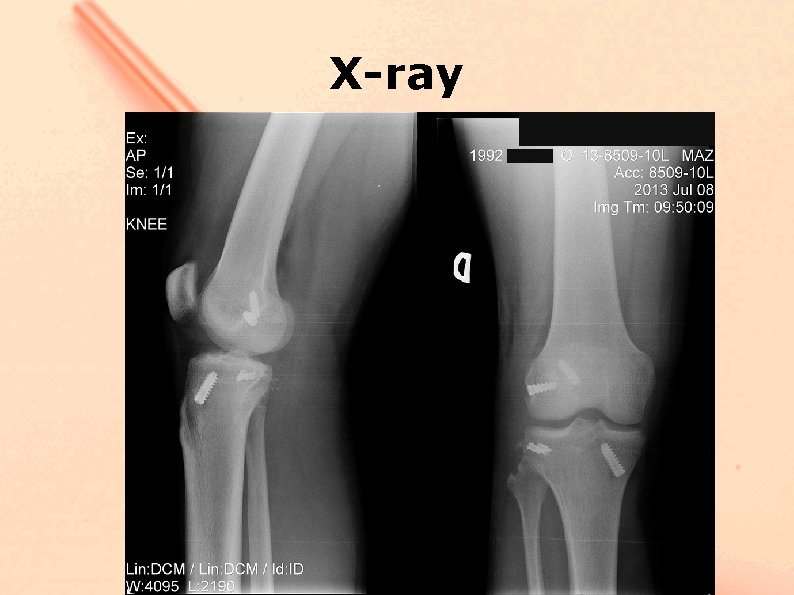

Postoperative X-ray

Case II 21 year male car accident injury. Right knee was involved. The dislocated limb was immobilized with brace. MRI – ACL, LCL, PLC, ITB injury was diagnosed neurology – partial CPN palsy.

Case II - Surgery was performed 8 days after injury - No signs of nerve repair was noted - Huge knee varus instability >15 degrees - External rotation 50 degrees - Pivot shift +++ - Lachman ++ - Anterior drawer ++

X-ray